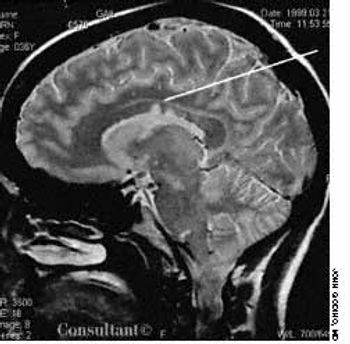

One week after an upper respiratory tract viral infection, a 36-year-old woman began to have progressive paresthesias of the lower extremities and right thorax. She sought medical evaluation 2 weeks later.